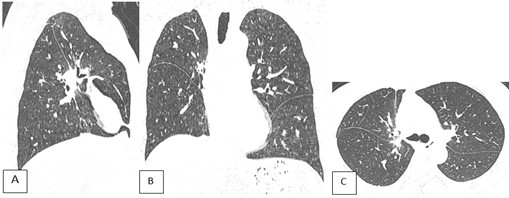

Hình 2. Phim CT ngực bệnh nhân khi vào viện, ảnh dựng MPR ở 3 bình diện. A: Axial; B: Sagital lệch phải; C: Coronal. Nốt bán đặc vị trí phân thuỳ II phổi phải, có dấu hiệu xâm lấn màng phổi tạng.

Hình 5. CT ngực BN chụp sau mổ 2 tháng, cửa sổ trung thất trước tiêm cản quang. A: SagitalB: Coronal; C: Axial. A-C: Quan sát thấy các đường may của Stapler khi phẫu thuật cắt thuỳ trên phổi phải (mũi tên)

Hình 6. CT ngực BN chụp sau mổ 2 tháng, cửa sổ nhu mô. A: SagitalB: Coronal; C: Axial. A-C: Phổi phải chỉ còn thuỳ giữa và dưới. Không thấy nốt bất thường nhu mô hai phổi.